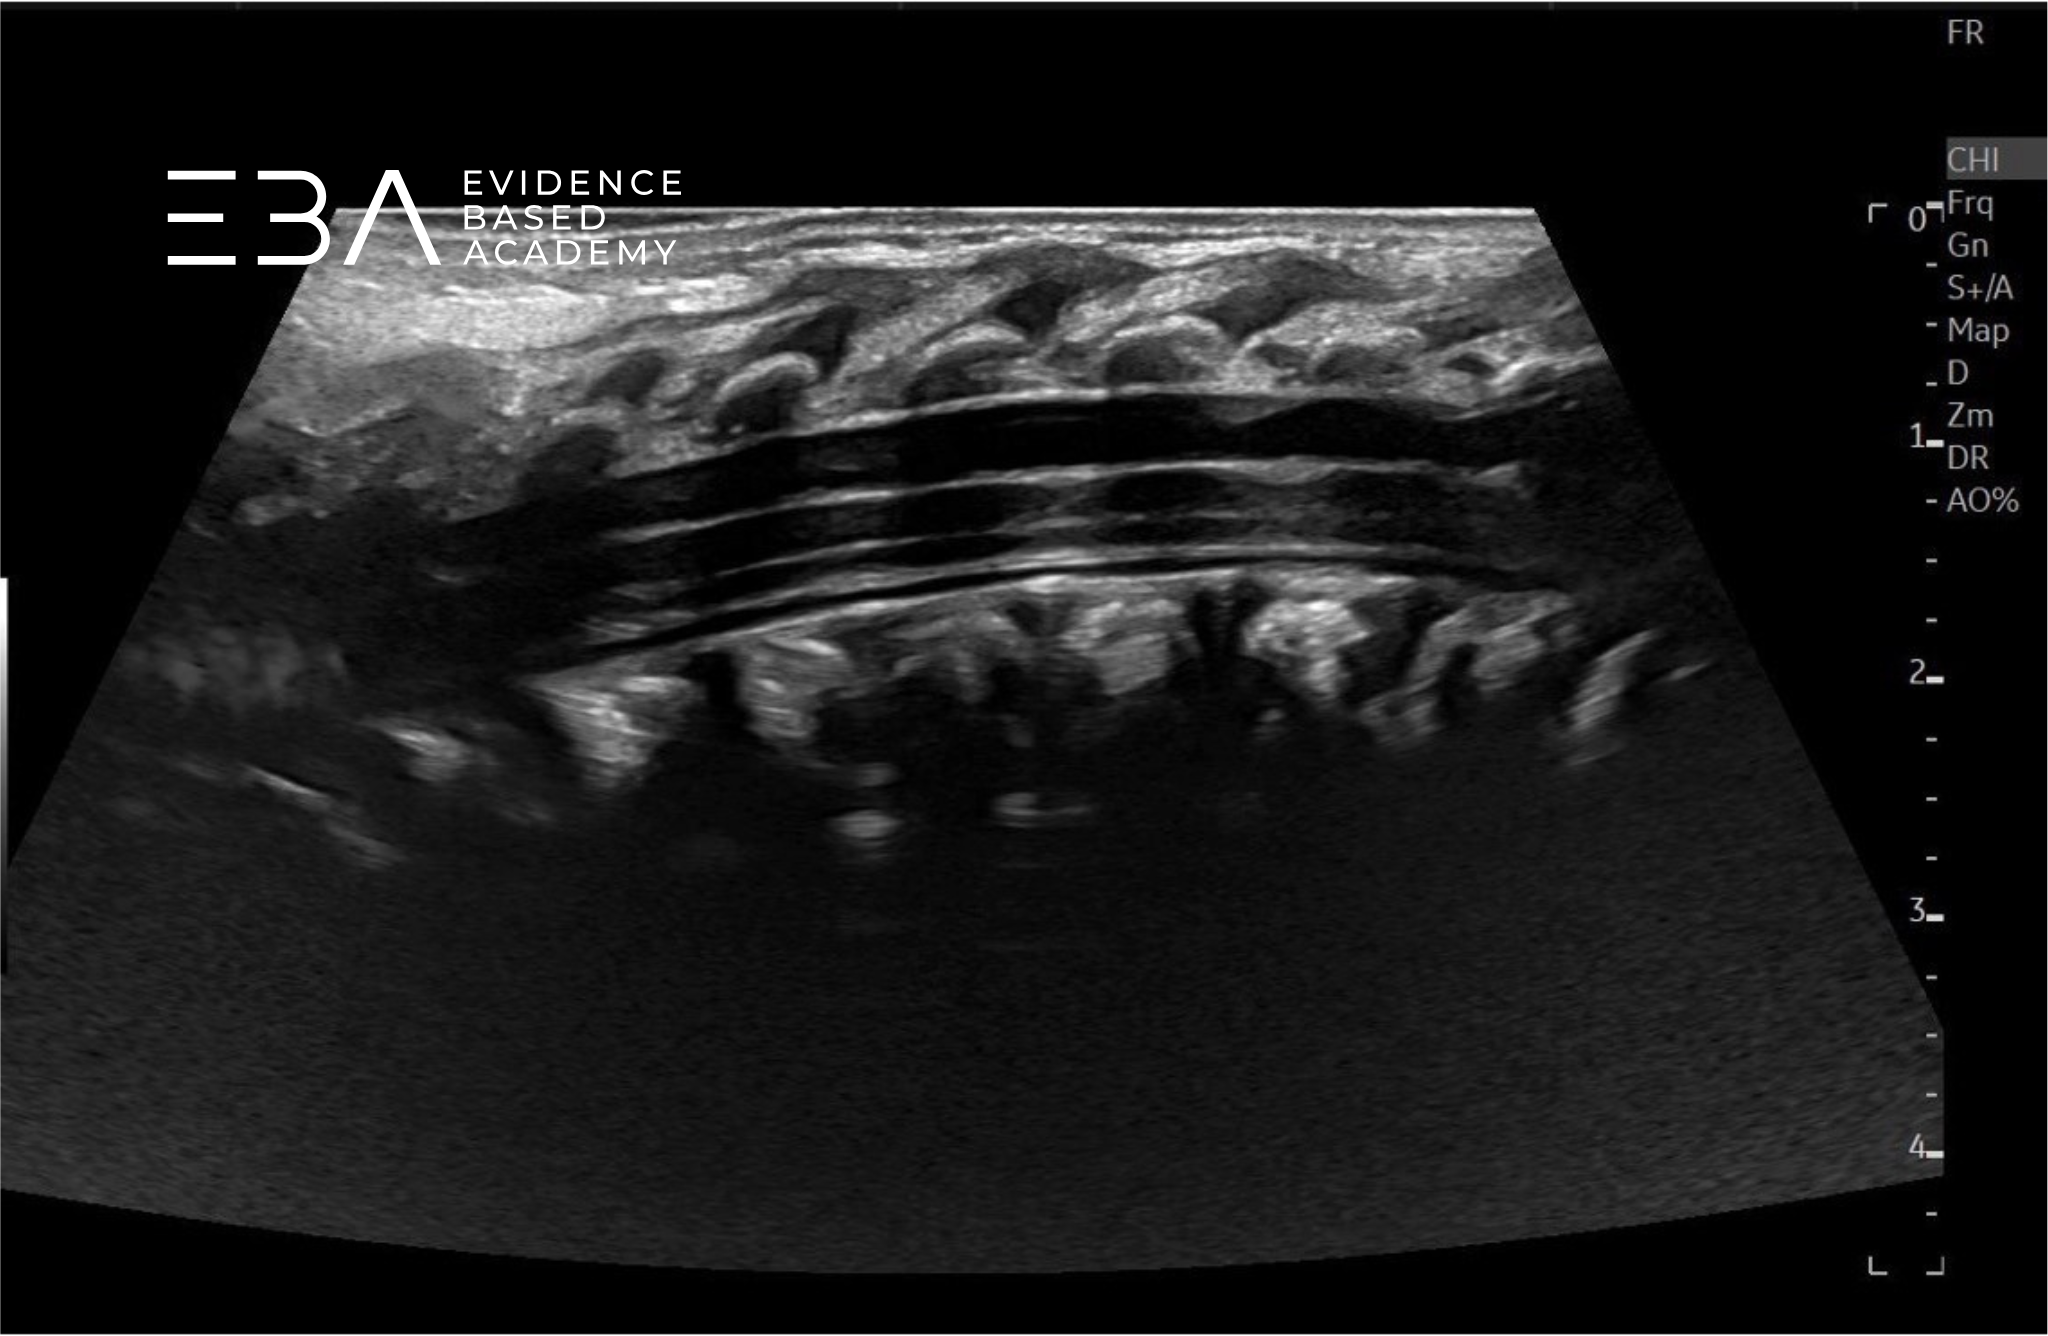

Worek oponowy i przestrzeń podpajęczynówkowa

Worek oponowy sięga do kręgu S2 i zawiera rdzeń kręgowy, nić końcową oraz ogon koński, otoczone bezechową przestrzenią podpajęczynówkową wypełnioną płynem mózgowo-rdzeniowym. Przestrzeń podpajęczynówkowa jest przerywana przez hiperechogenne liniowe korzenie nerwowe oraz więzadła zębate.

Granica worka oponowego stanowi echogeniczne połączenie między oponą twardą a pajęczynówką, widoczne jako równoległe linie na obrazach podłużnych i koncentryczne linie na obrazach poprzecznych. Przestrzeń podtwardówkowa jest przestrzenią potencjalną między tymi warstwami, niewidoczną przy braku płynu lub krwi. Tłuszcz nadtwardówkowy znajduje się grzbietowo i brzusznie względem granicy opony twardej.

fot. 19

Kanał kręgowy, przekrój podłużny odcinka krzyżowego. W bezechowej przestrzeni podpajęczynówkowej widoczne są echogeniczne pasma włókien nerwowych (strzałki).